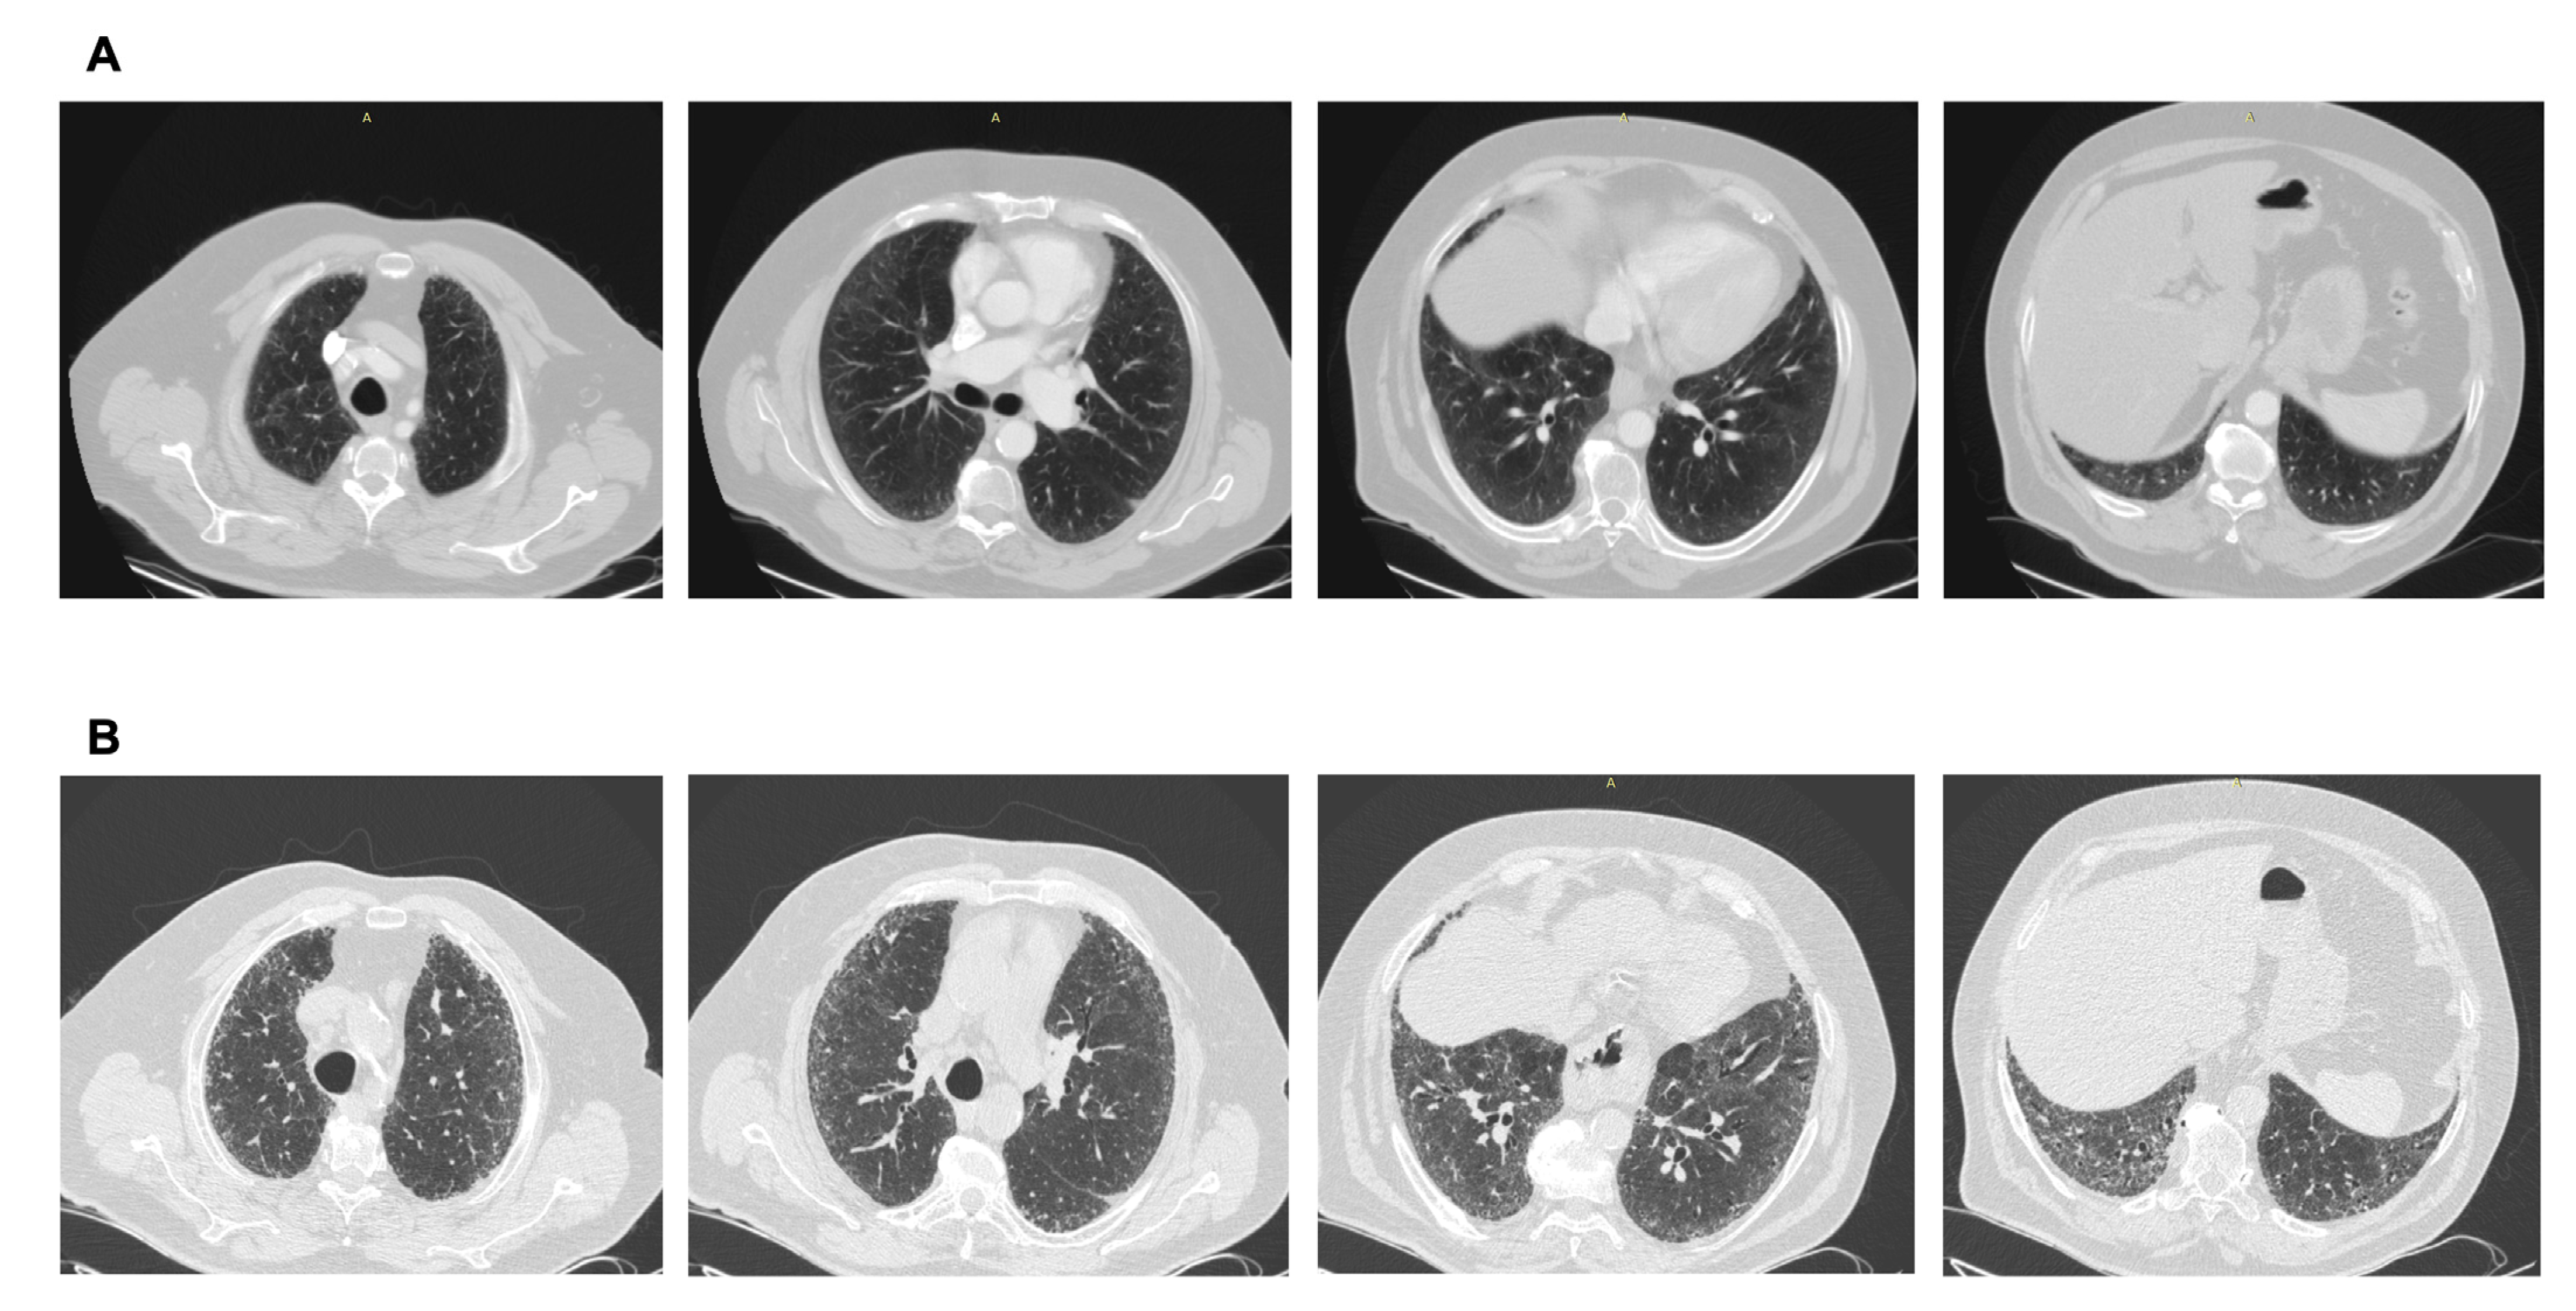

Figure 3.

(A) CT scan performed after a car accident in an asymptomatic individual. Note the mild ground glass subpleural changes and the subtle mosaic attenuation. No investigation/intervention followed. (B) Three years later, the patient became symptomatic, with remarkable progression to a fibrotic pattern. A heavy exposure to pigeons was revealed. Final diagnosis: Hypersensitivity pneumonitis. Avoidance of the causative factor would possibly have attenuated progression.